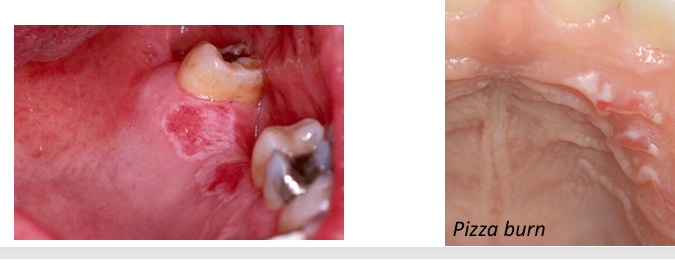

thermal burn

-acute, heat-induced damage to oral mucosa: tender/sensitive, may be erythematous or covered by white/gray film

-resolves over 2-3 weeks

chemical burn (non-specific irritant contact stomatitis)

-white, necrotic plaque: variable erythema, may or may not be ulcerated

-history of exposure to caustic irritant: aspirin, topical anesthetic, hydrogen peroxide, formocresol, whitening strips

-management: removal of irritant, topical steroids as needed